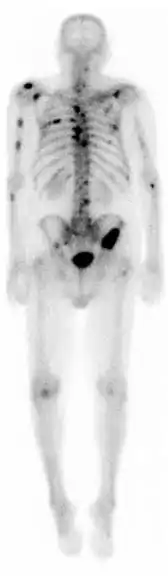

![]() A nuclear medicine whole-body bone scan. The nuclear medicine whole-body bone scan is generally used in evaluations of various bone-related pathology, such as for bone pain, stress fracture, nonmalignant bone lesions, bone infections, or the spread of cancer to the bone. | |

A bone scan or bone scintigraphy /sɪnˈtɪɡrəfi/ is a nuclear medicine imaging technique of the bone. It can help diagnose a number of bone conditions, including cancer of the bone or metastasis, location of bone inflammation and fractures (that may not be visible in traditional X-ray images), and bone infection (osteomyelitis).[1]